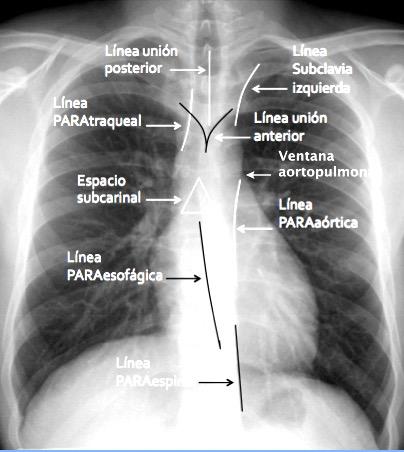

7. LÍNEAS,√BANDAS Y ESPACIOS. PROYECCIÓN PA

Línea paratraqueal derecha

Línea paratraqueal izquierda

Espacio subcarinal

Línea para-aórtica

Líneas paraespinales

Banda traqueal posterior

Banda retroesternal

Triángulo de Raider